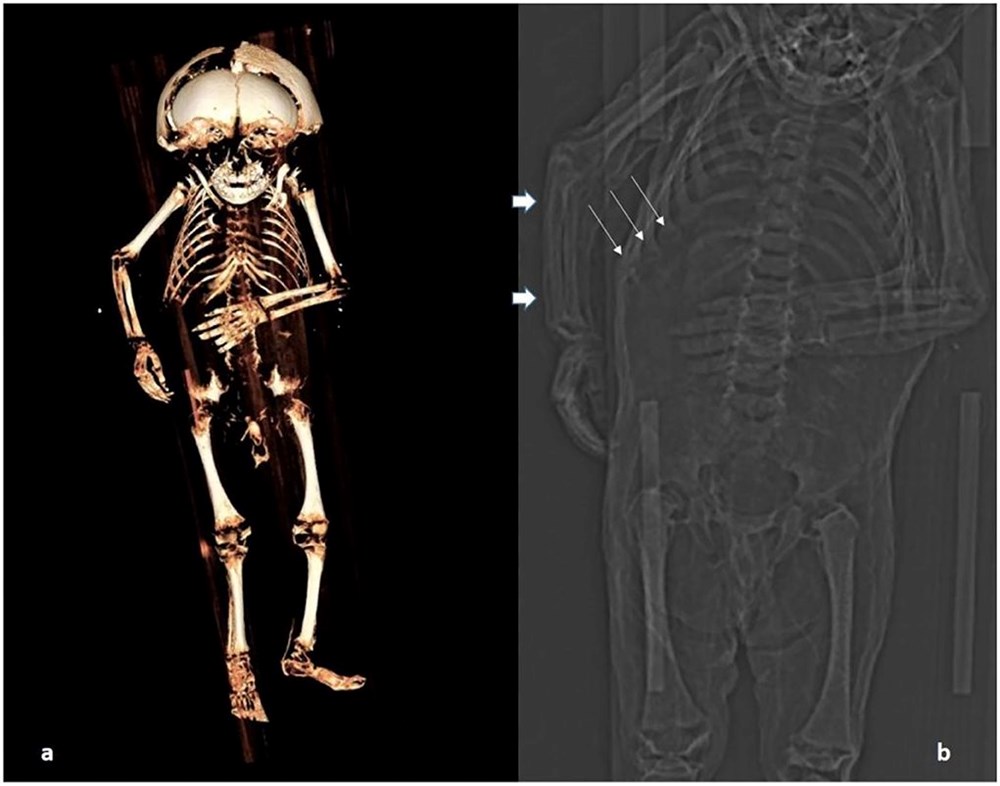

Kafatası deforme olan ve biraz küçük olan tahta bir tabuta gömülen küçük çocuğun vücudu hem obez hem de yetersiz beslenmiş gibi görünüyordu. Frontiers in Medicine’de yayınlanan çalışmada araştırmacılar, bulguların tarihi Avusturya aristokrat toplumuna ender bir bakış açısı sağlayabileceğini söyledi.

Bilim adamları, CT taramasını kullanarak, mahzen koşullarında doğal olarak mumyalanan mumya üzerinde ‘sanal otopsi’ yapabildiler. İyi korunmuş yumuşak doku, çocuğun bir erkek olduğunu, yaşına göre fazla kilolu olduğunu gösterdi ve radyokarbon tarihlemesi ise MS 1550 ile 1635 arasında bir ölüm tarihini gösterdi.

Araştırmacılar, vücudun kemiklerinin oluşumunu ve uzunluğunu ve ayrıca diş patlamasının kanıtlarını inceleyerek, çocuğun öldüğünde yaklaşık bir yaşında olduğunu tahmin edebildiler. Kemikler ayrıca, çocuğun iyi beslenmesine rağmen bozuk kaburgalarında raşitik tespih belirtileri bulundu. Bu durum, raşitizm (D vitamini) ve iskorbüt (C vitamini) gibi spesifik vitamin eksiklikleri ile ilişkili hastalıklardan kaynaklanır.

Nerlich, “Önceki popülasyonların yüksek aristokrat bebeklerinin yaşam koşullarını yeniden gözden geçirmeliyiz” dedi.